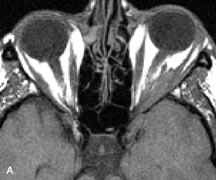

Extraocular muscle enlargement in patients with thyroid-associated orbitopathy is demonstrated equally well with CT and MRI studies. However, the superior tissue contrast on MR images reveals better details of the relationships of the optic nerve to the thickened muscles at the orbital apex (Fig. 16).50 In addition, MRI may be able to differentiate between muscles that are enlarged as a result of edema and active inflammation and those enlarged because of fibrosis by their T2 relaxation times.21 Quantitative MRI was not found to be accurate in predicting the success of low-dose orbital irradiation.51 However, a muscular index relating the diameters of the rectus muscles to the bony orbital dimensions was useful in predicting optic nerve compression.52

Fig. 16. A-C, T1-weighted MR scans obtained with a high-resolution surface coil demonstrate fusiform enlargement of the extraocular muscles. The medial, lateral, and inferior rectus muscles are especially involved. Note the relative sparing of the tendinous insertions, a finding characteristic of this disease process, as well as fatty infiltration of the lateral and inferior rectus muscles. There is marked proptosis, best visualized on the sagittal image (A), and mild crowding of the optic nerve at the orbital apex.